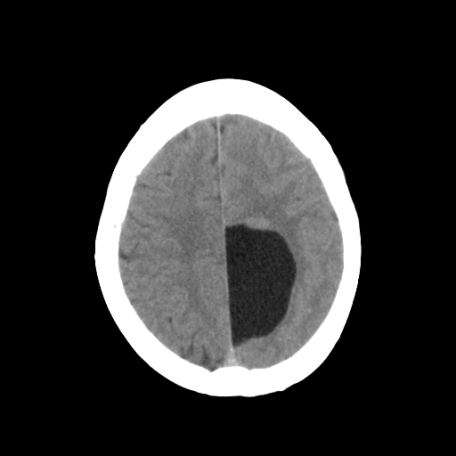

以下是引用深泽交通医院在2009-8-7 12:18:00的发言:[br]有壁结节,考虑囊变型胶质瘤

以下是引用帅河马在2009-8-7 13:50:00的发言:[br][quote]以下是引用深泽交通医院在2009-8-7 12:18:00的发言:[br]有壁结节,考虑囊变型胶质瘤

以下是引用卜一在2009-8-7 15:50:00的发言:[br]囊变性脑膜瘤!支持!

以下是引用随光逐影在2009-8-7 15:58:00的发言:[br]考虑左侧顶叶胶质瘤,不排除左侧镰旁脑膜瘤;建议行进一步检查。

以下是引用shibing在2009-8-7 16:36:00的发言:[br]增强扫描